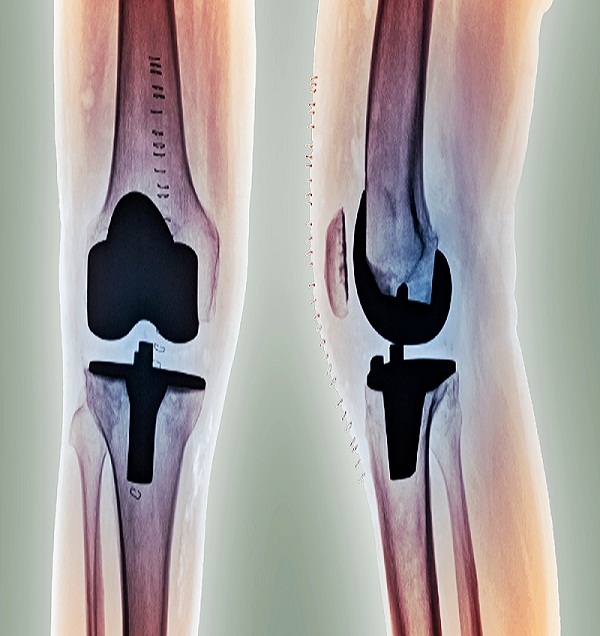

Knee Joint Replacement

Knee replacement surgery is often a last resort treatment for an injured or damaged knee joint. This procedure takes a few hours, but recovery and rehabilitation can last months. Some of the risks of this procedure are infection, nerve damage, and knee stiffness.

Knee joint replacement is a procedure that involves replacing an injured or ailing knee with an artificial joint, or prosthesis. Another name for this procedure is knee arthroplasty. Knee replacements are a very common surgery.

The prosthesis is made of metal alloys, plastics, and polymers. It mimics the function of a knee. Replacement knees can fit your needs and specifications. When selecting a prosthetic knee, your doctor will take into account your:

The procedure to remove your old knee and replace it with a prosthesis usually takes less than two hours, but recovery and rehabilitation can last months.